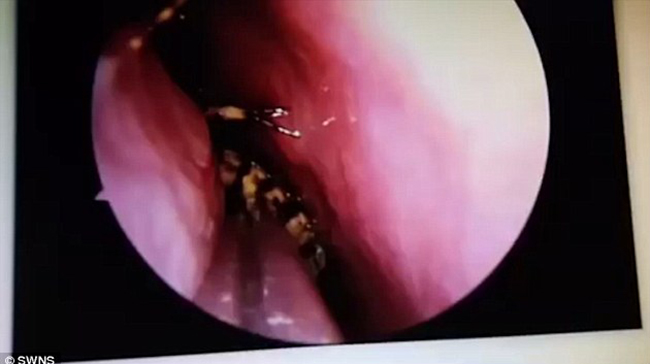

Cảm thấy đau đầu và nóng bên trong đầu, Sevi đã đến gặp bác sĩ để được tư vấn. Sau khi thực hiện các xét nghiệm, bác sĩ hết sức ngạc nhiên khi phát hiện có một con gián sống đang 'đi lại' trong hộp sọ của bệnh nhân. Cuộc phẫu thuật đã được thực hiện ngay sau đó để kéo con gián ra ngoài.

Bỗng cảm thấy đầu nóng như thiêu đốt từ bên trong, cô Sevi, người Ấn Độ đã nhanh chóng tới Bệnh viện Đại học Y Stanley, thành phố Chennai nước này để kiểm tra sức khỏe. Tại đây, các bác sĩ đã bất ngờ phát hiện ra có một con gián vẫn còn sống đang làm tổ trong hộp sọ của cô.

Con gián đã chui vào hộp sọ cô Sevi qua đường lỗ mũi.

Kết quả siêu âm cho thấy, con gián đang nằm trên nền sọ, vị trí giữa hai mắt. Dù đã trú ngụ ở đó một thời gian nhưng nó vẫn sống.

Để gắp được con gián ra khỏi hộp sọ của người phụ nữ, các bác sĩ đã phải sử dụng tới máy hút và nhíp trong ca phẫu thuật kéo dài 45 phút đồng hồ.

Bác sĩ M N Shankar, trưởng khoa Tai - Mũi - Họng của bệnh viện cho biết, đây là ca bệnh hy hữu nhất mà ông từng tiếp nhận trong suốt hơn 30 năm làm nghề y. Và nếu không nhanh chóng gắp bỏ con gián ra, não bộ của cô Sevi sẽ bị nhiễm trùng.

Con gián đã chui được vào gần não của người phụ nữ.